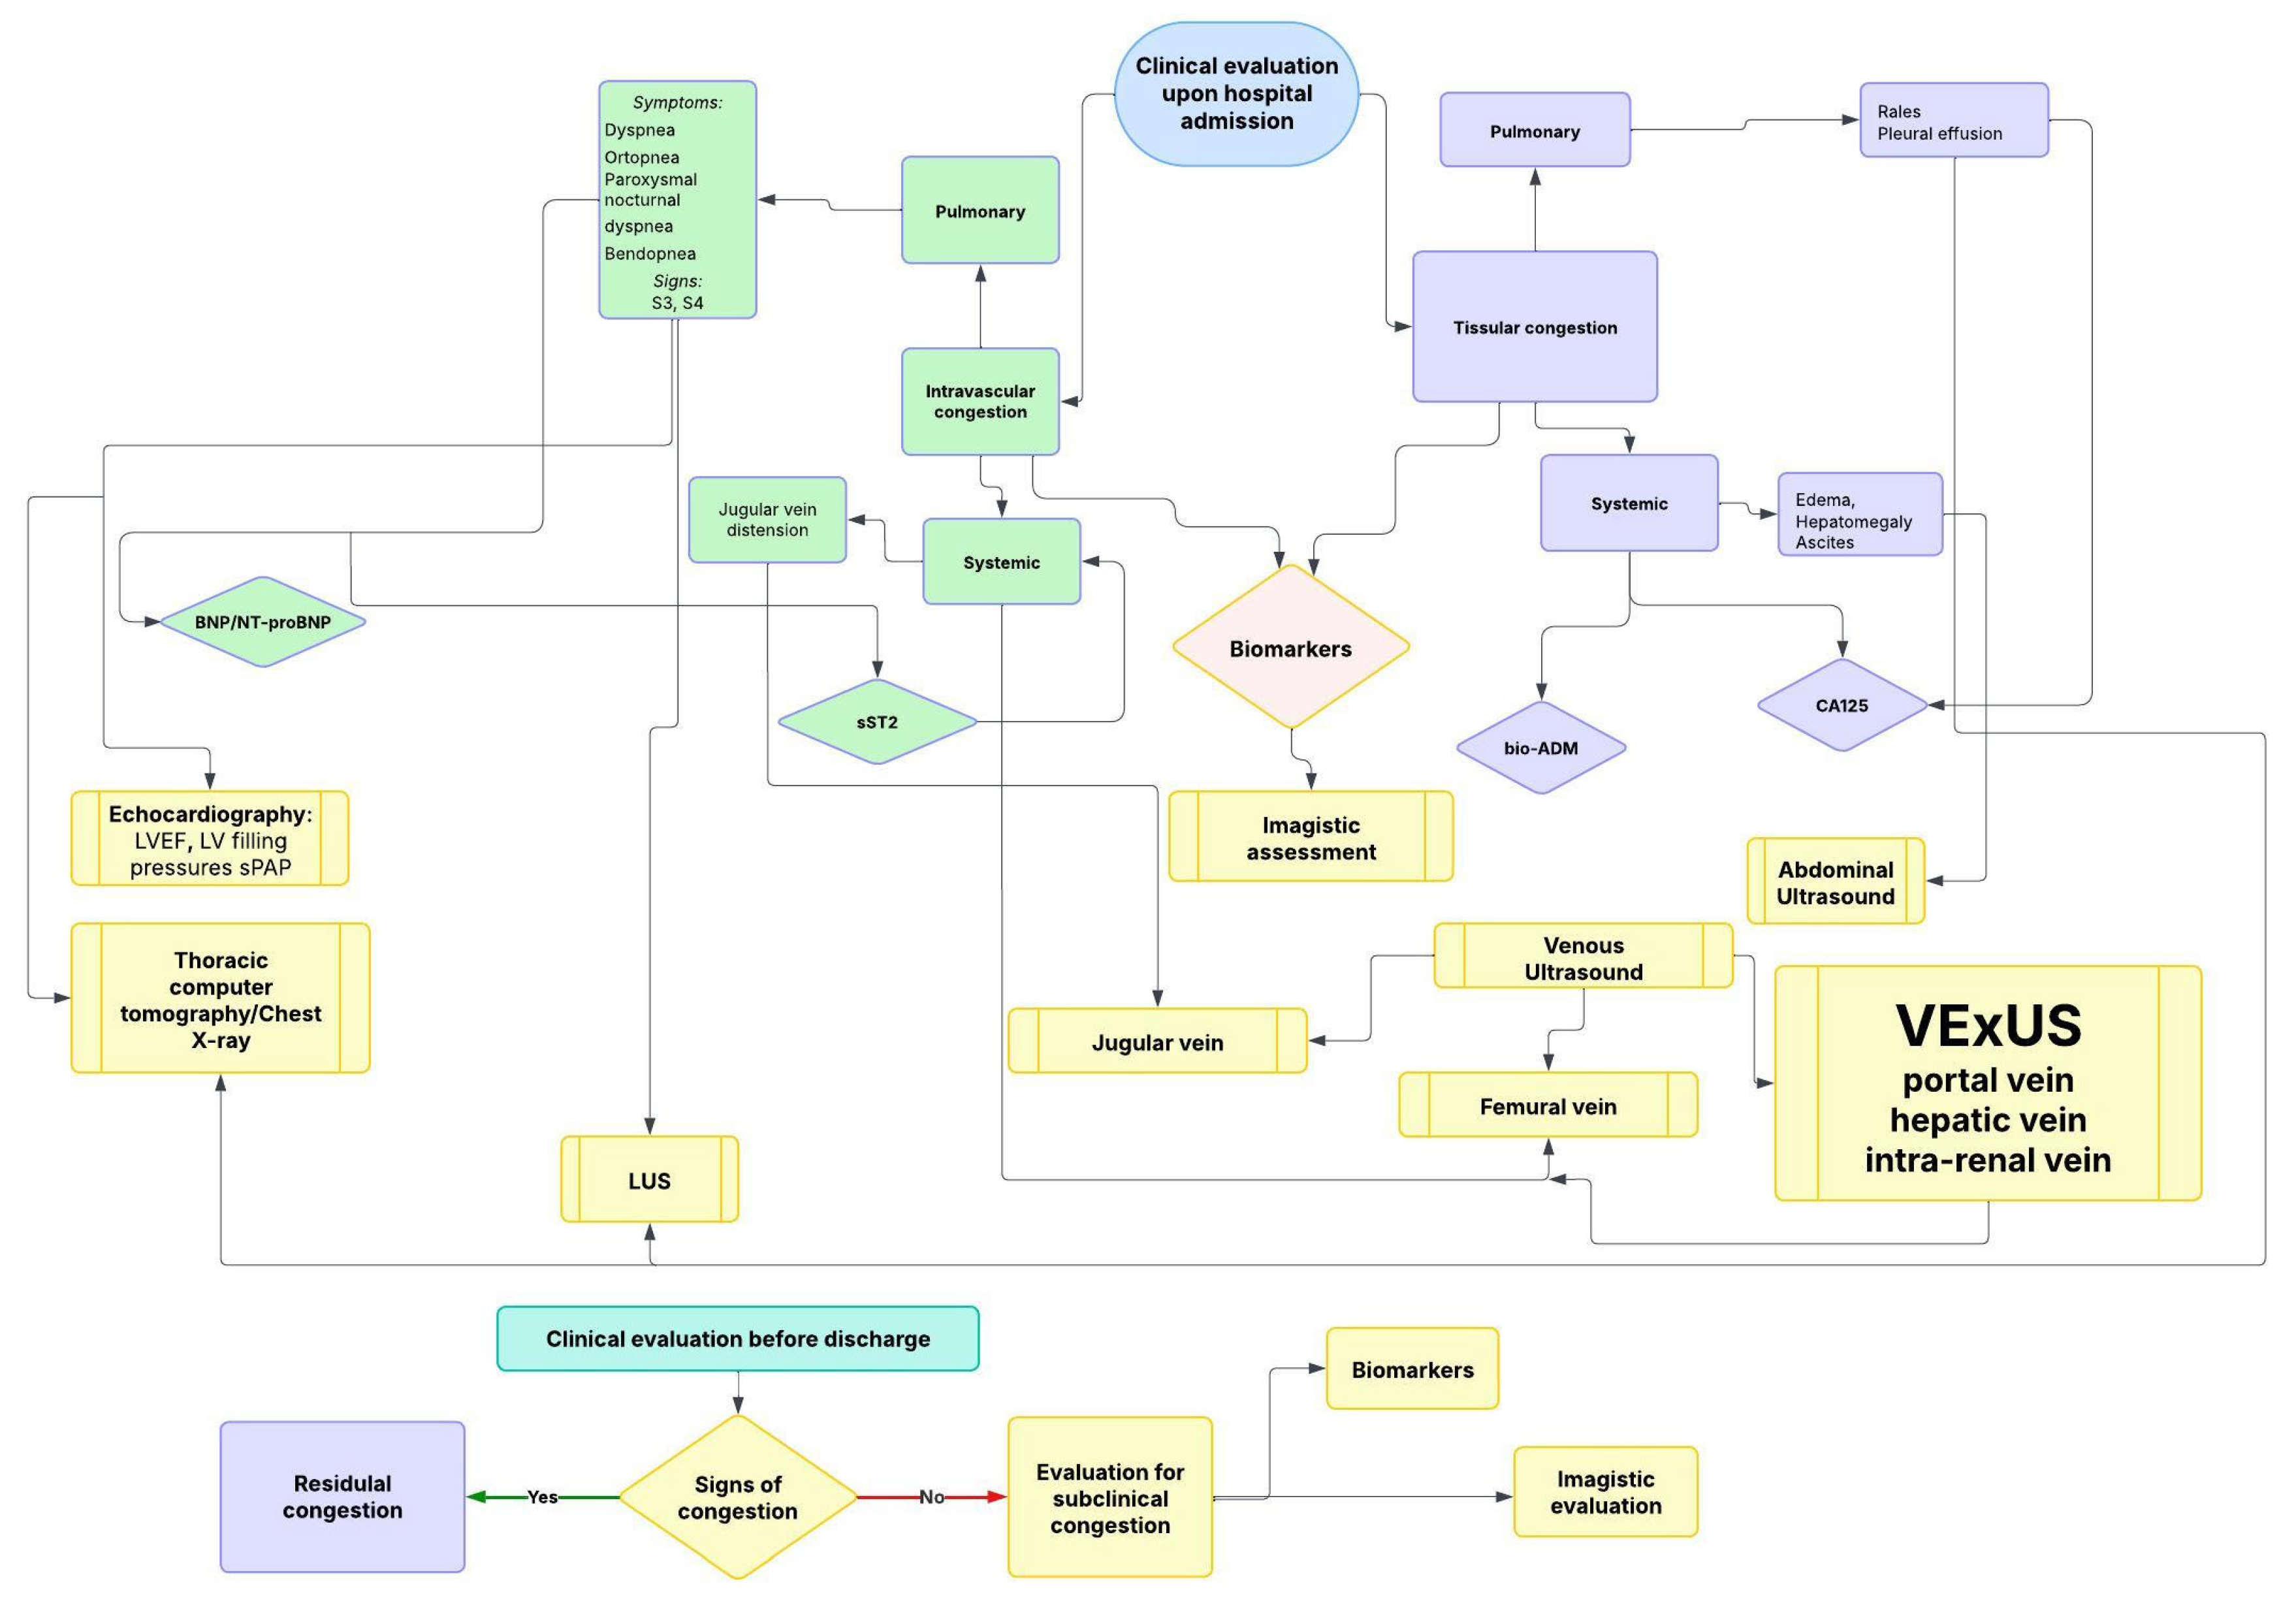

5. The Role of Imaging in Evaluating Congestion

5.1. Intravascular Pulmonary Congestion

5.1.1. Lung Ultrasound (LUS)

Pleural Effusion

5.1.2. Thoracic Computer Tomography and Chest Radiography

5.1.3. Echocardiography

5.2. Intravascular Systemic Congestion

5.2.1. Ultrasound Assessment of Systemic Venous Congestion: Role of VExUS

5.2.3. Jugular Vein Ultrasound

5.2.4. Femural Vein

5.3. Tissue Systemic Congestion

5.3.1. Peripheral Edema

5.3.2. Ascites

7. Integrated Multimodal Assessment and Clinical Application